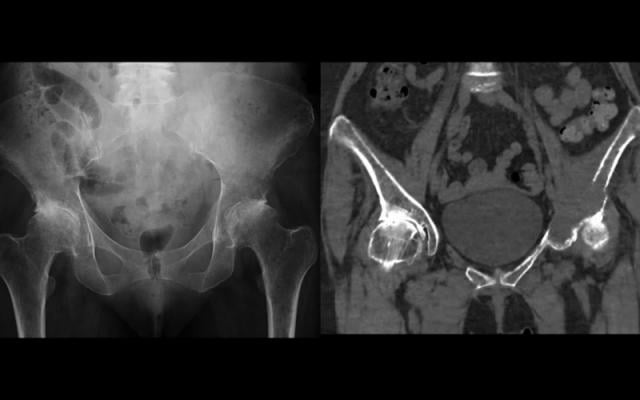

Multiple myeloma is a monoclonal gammopathy and is the most common primary malignant bone neoplasm in adults. Below the columns are the numbers of positive, negative and missing results of each imaging modality shown. Learn how doctors and nurses at memorial sloan kettering make pain control a priority. Multiple myeloma (kahler's disease) is a malignant plasma cell dyscrasia characterized by uncontrolled proliferation and the diffuse infiltration of monoclonal plasma cells in the bone marrow. It sounds like a lot (and it is!) but none are that invasive or painful, with the exception of the bone marrow biopsy, but even that. Multiple myeloma is the most common primary malignant neoplasm of the skeletal system. Multiple myeloma (mm) is an incurable plasma cell malignancy of the bone marrow. Assigning a stage and a risk category. Single lytic lesion (a) and two lytic lesions of the medial part and. Multiple myeloma is the second most common type of blood cancer after leukemia. Usually skeletal survey of the bone is performed to diagnose diseases such as multiple myeloma. Smouldering multiple myeloma is typified by a serum paraprotein of >30 g/l or a bone marrow plasmacytosis of >10% (table 1). Learn more about the symptoms, causes, diagnosis, risk factors, and treatment of multiple myeloma.

Multiple myeloma | Radiology Case | Radiopaedia.org from images.radiopaedia.org Assigning a stage and a risk category. Multiple myeloma is when plasma cells become cancerous and produce bone tumors called plasmacytomas. The appearance is highly suggestive of, but not completely diagnostic for, multiple myeloma. Multiple myeloma (mm) is an incurable plasma cell malignancy of the bone marrow. Multiple myeloma is a monoclonal gammopathy and is the most common primary malignant bone neoplasm in adults. Not all tests listed below will be used for every person. Dinter dj, neff wk, klaus j, böhm c, hastka j, weiss c, et al. Learn more about the symptoms, causes, diagnosis, risk factors, and treatment of multiple myeloma.

Preoperative X-ray presentation of multiple myeloma ... from www.researchgate.net Multiple myeloma (mm), also known as plasma cell myeloma and simply myeloma, is a cancer of plasma cells, a type of white blood cell that normally produces antibodies. The appearance is highly suggestive of, but not completely diagnostic for, multiple myeloma. The hallmark biomarker in blood or urine is a monoclonal immunoglobulin, the monoclonal protein. Learn how doctors and nurses at memorial sloan kettering make pain control a priority. Sometimes multiple myeloma is diagnosed when your doctor detects it accidentally during a blood test for some other condition. Multiple myeloma is cancer that starts in the bone marrow's plasma cells. Background bone lesions are a key feature of multiple myeloma and for many years the conventional skeletal x‑ray survey following the paris. Multiple myeloma (mm) is an incurable plasma cell malignancy of the bone marrow.